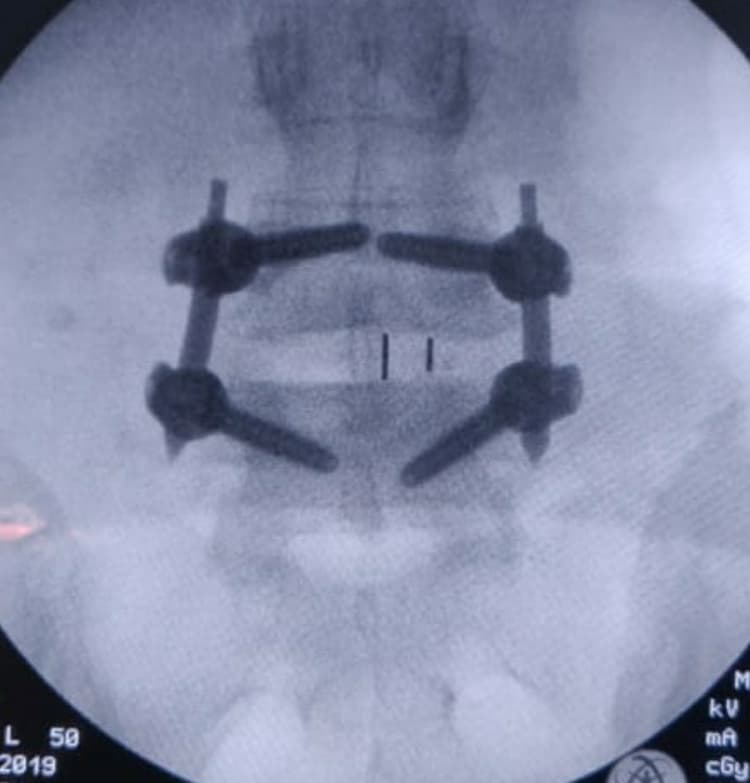

Procedure: The patient underwent Transforaminal Lumbar Interbody Fusion (MIS TLIF).